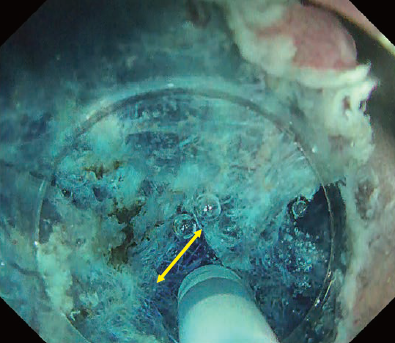

In this case, introduction into the submucosal layer appears more difficult than usual because the mucosa is thickened due to inflammation. We therefore applied the WPM². This technique was originally proposed for duodenal ESD but can be a powerful tool when introduction into the submucosal layer is difficult. As shown in Fig. 9, it effectively visualizes the tissue to be cut by properly using the tapered hood. Because immersion expands the visual field, the knob-shaped tip of DualKnife J can be precisely applied to the point to be cut, enabling truly precise ESD.

Once the DualKnife J has been introduced into the submucosal layer, you can use the PCM to excavate the central part and expose the fibrotic region (Fig. 9). After that, you can spread the pocket in the usual way and complete en-bloc resection.

Fig. 9